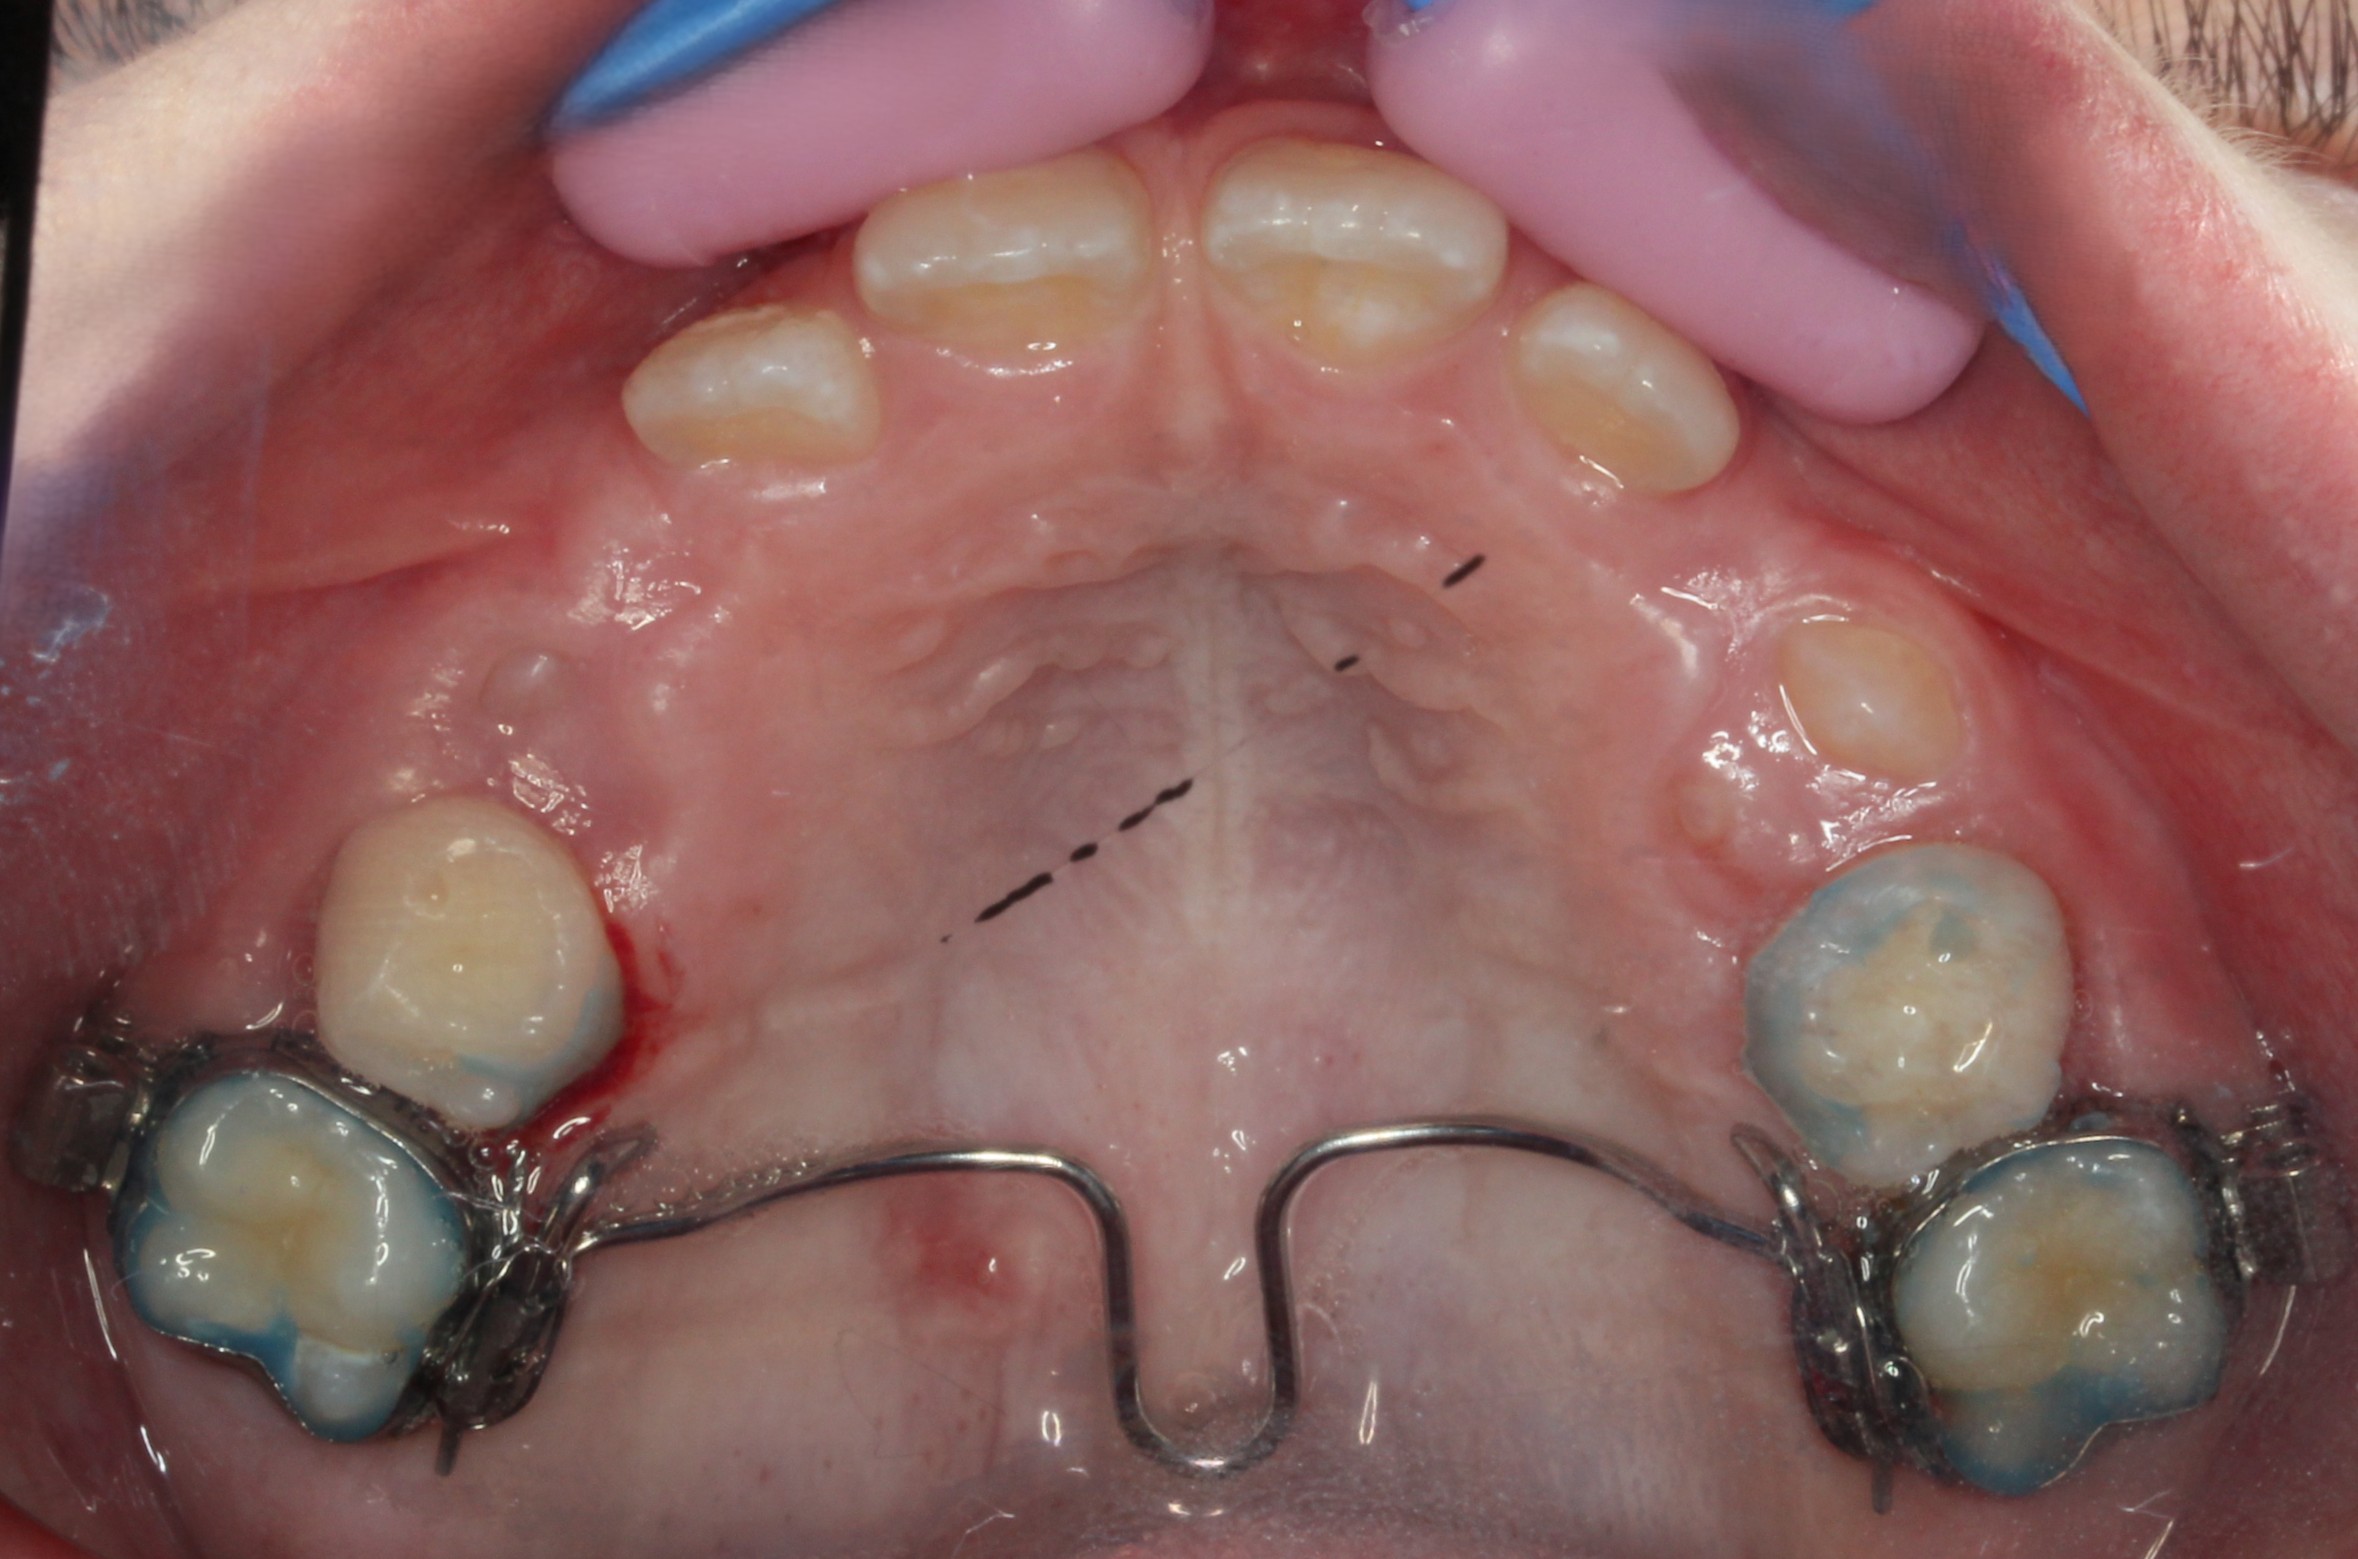

TPA - Transpalatal Arch

TPA er en fastsiddende gane bøjle i metal der sikrer en forankring under en

tandregulering.

En TPA er en lille metal stang der formes præcis til din gane, som sidder fast i to bånd der er cementeret på dine to første kindtænder.

Bøjlen stabiliserer de kindtænder med metal bånd rundt om, så der ikke mistes plads i overkæben.